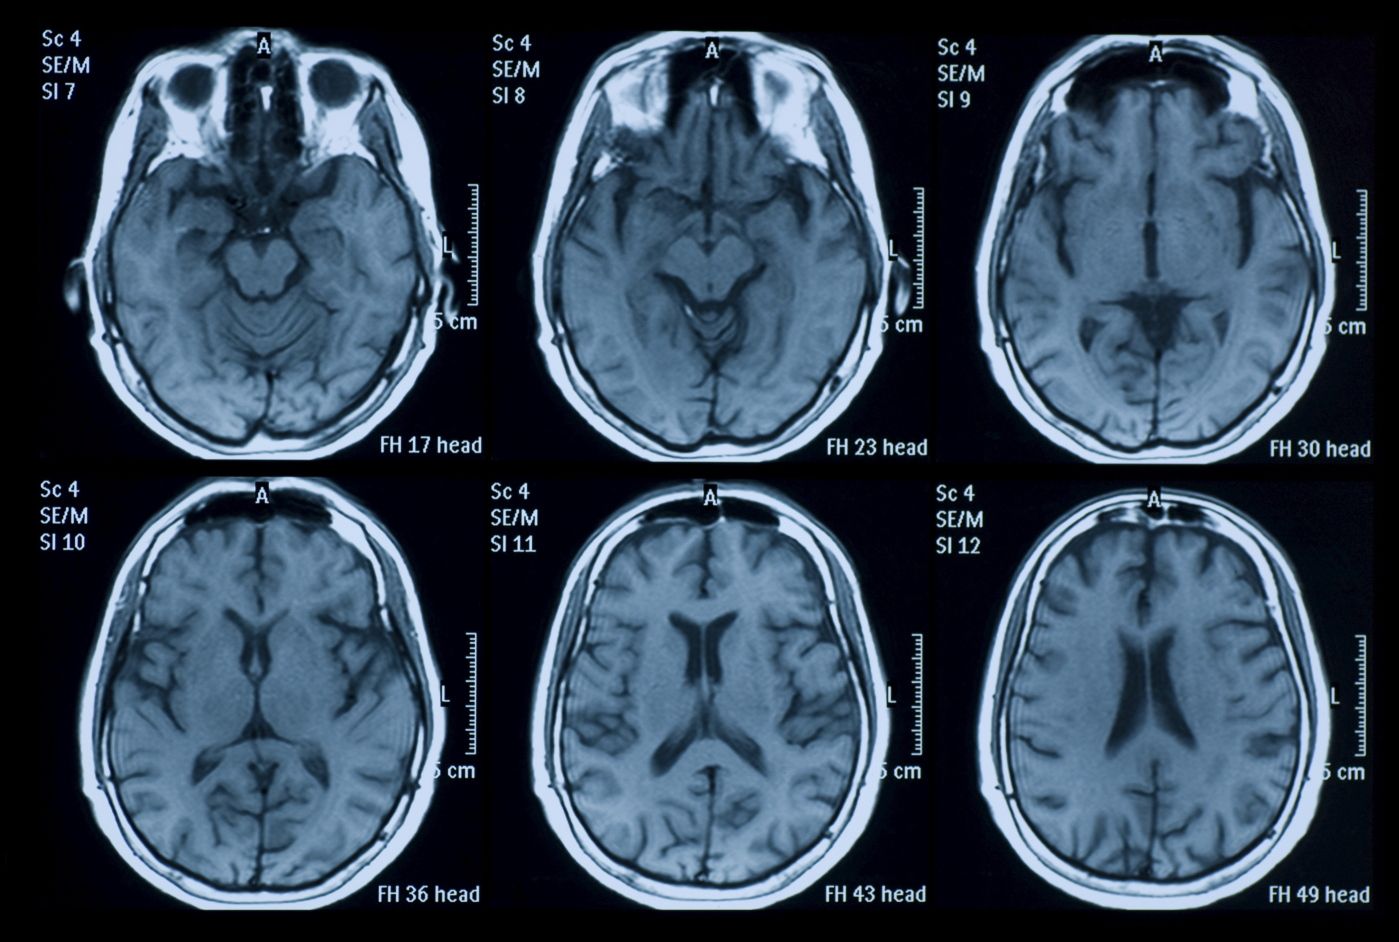

HJERNEKART: Er det mulig å se – via for eksempel en MRI-maskin – hva vi tenker på? Til en viss grad, ifølge forskere ved University of California, Berkeley. De har laget et interaktivt hjernekart som kan vise hva slags kategori ord – for eksempel «dyr» – du leser om, eller hører om. Formålet med forskningen var å sammenlikne det å lese en historie med å høre den samme historien, noe de fant ga noenlunde de samme utslagene på MRI-skanningen. Men studien mer enn antyder at dette også kan brukes til å gi hint om hva man tenker på. (Journal of Neuroscience) BV